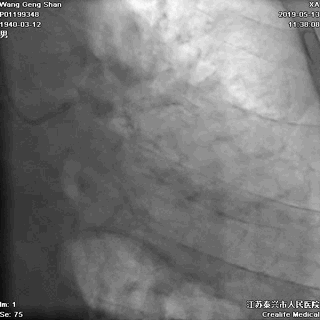

05 LM-LAD支架植入

右头位定位

蜘蛛位定位